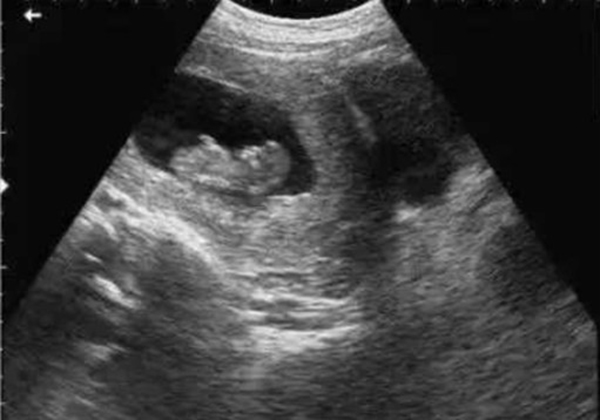

? 超聲檢查(B超/彩超):它利用超聲波的反射原理成像,就像“用聲音給身體拍照片”,沒有任何輻射。無論是孕期產(chǎn)檢(觀察胎兒發(fā)育)、腹部檢查(排查肝脾膽囊問題),還是甲狀腺、乳腺等淺表器官檢查,超聲都是首選。而且超聲檢查靈活便捷,還能實(shí)時(shí)動(dòng)態(tài)觀察器官運(yùn)動(dòng)(比如心臟跳動(dòng)、胎兒胎動(dòng)),是臨床中應(yīng)用最廣泛的“安全檢查”。